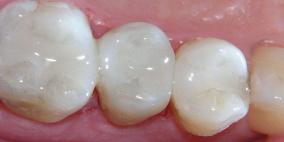

ابتكار حشوات أسنان أبدية